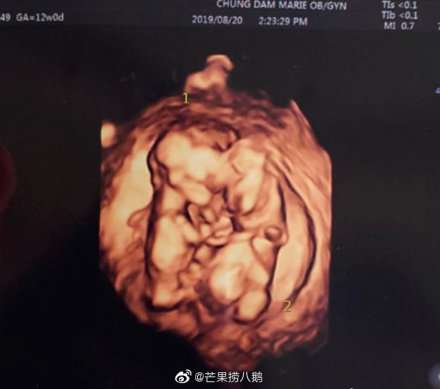

双胞胎b超照

28日,金律喜发文表示二胎怀上了双胞胎:非常感谢听到我怀了双胞胎的消息而发来祝贺的各位,能感觉到肚子的两个孩子在紧紧相依地长大,再次对祝福我们的各位表示感谢。8月16日,FTISLAND成员崔敏焕通过个人INS宣布了妻子怀二胎的喜讯。